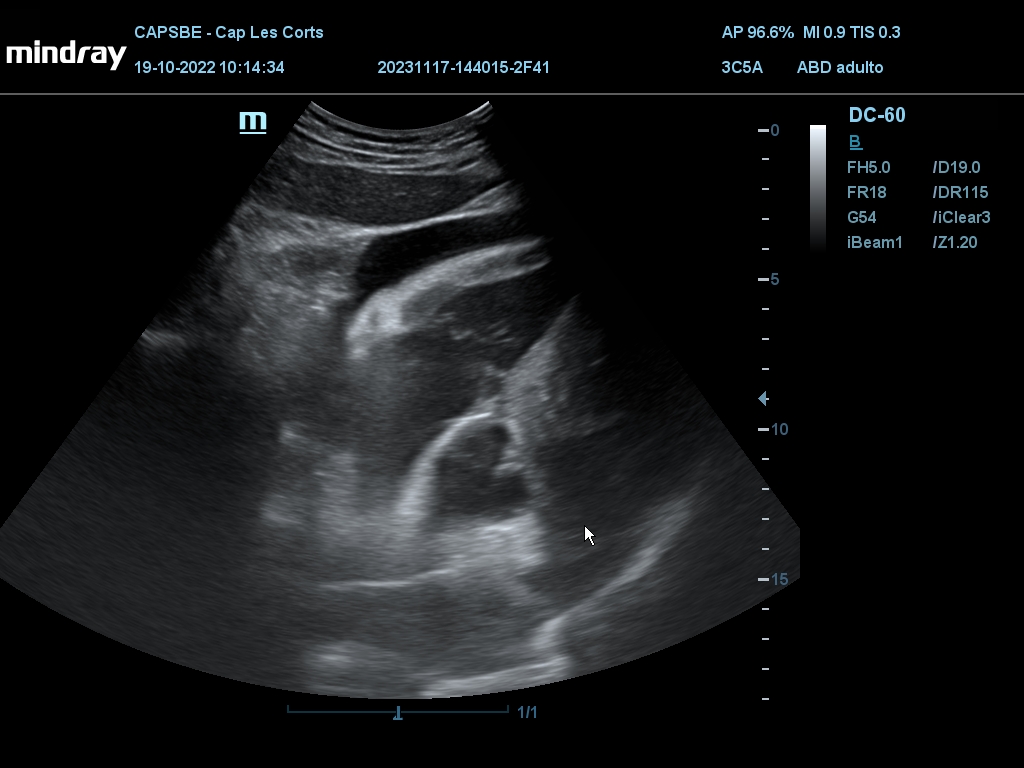

Hallazgos ecográficos

Derrame pericárdico. Vesícula biliar con grosor parietal de 1,6 cm, heterogénea, no se moviliza con cambios posturales. Quistes renales derechos, mayor de 7 cm. Aorta ateromatosa y aneurismática de 36 x 42 mm. Sin líquido intraabdominal.

(Se adjuntan imágenes del derrame, engrosamiento biliar, riñón derecho y aneurisma de aorta).

• Ecocardiografía: FE 50%. Ventrículos engrosados, aurícula izquierda dilatada, derrame pericárdico. Signos sugestivos de infiltración (posible amiloidosis).